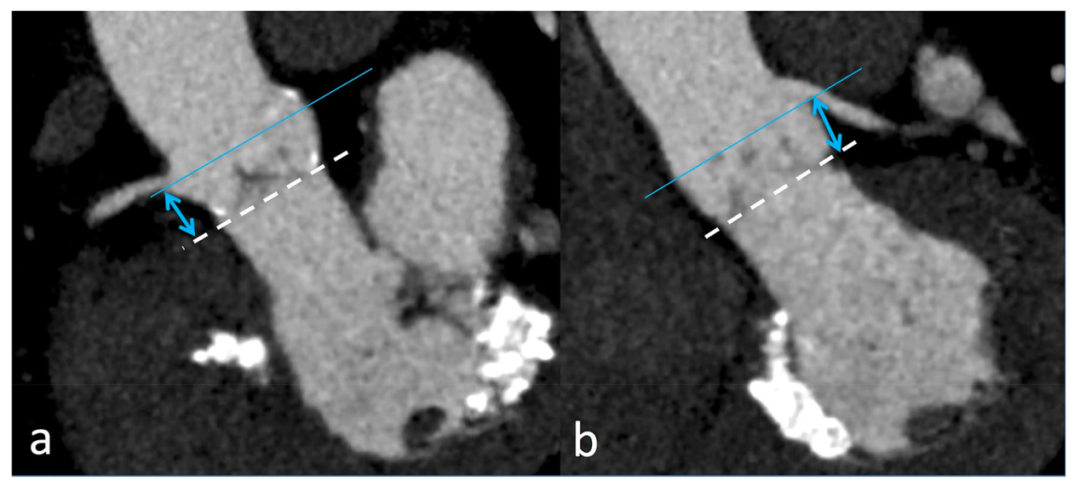

主动脉根部连接心脏和体循环,是一个复杂而精密的结构,由瓣环、主动脉瓣、Valsalva 窦和窦管交界处组成。在 CT 图像上,主动脉瓣环是对应于主动脉瓣基底部的解剖部位,三个瓣叶的最低插入点(铰链点)形成的环平面,位于心室-动脉交界处的正下方。准确测量主动脉瓣环和主动脉根部是评估TAVI可行性、正确的术前计划和装置选择(瓣膜尺寸和设计)的基础。沿常规解剖平面(冠状面和矢状面)重建或单斜重建粗略测量瓣环尺寸是不可行的。为得到可靠的测量结果,必须提供最佳质量的图像以及对重建斜面的正确定位,这是装置选择的基础。图2显示了如何从传统平面开始采用双斜入路获得主动脉瓣环的正确横截面图像。瓣环尺寸测量需要标准化和可重复的方法。瓣环尺寸的测量应包括长轴和短轴直径、截面积和周长(图3),所有测量值都可通过(半)自动衰减/基于Hounsfield 单元的轮廓检测得到。面积和周长得出的有效直径是在植入装置后瓣环为正圆形的几何假设下计算的。然而,这些方法存在固有误差,并且当瓣环形状特别偏心时,可能导致所选假体尺寸过小或过大,从而导致瓣周漏或植入的瓣膜展开不完全的风险。瓣环在心动周期中也会发生构象和尺寸变化:其形状在收缩期更偏圆形,在舒张期主要呈卵圆到椭圆形。由于与左心室射血相关的径向力的增加,与舒张期相比,收缩期瓣环的短轴直径、截面积和周长更大。因此,如果可获得多相数据,应首选在收缩期重建的图像来测量瓣环尺寸,因为在不同时相变化很大的患者中,使用舒张期测量可能会导致 TAVI 假体尺寸过小,导致瓣周漏的风险增加(图 4)。然而,在心率较快或心律失常的患者中,收缩期图像更容易受到心脏跳动伪影的影响,如果在扫描采集期间进行剂量调制,则通常会表现为图像噪声增加。在这些情况下,舒张期图像会提供更好的图像质量。主动脉瓣狭窄通常以瓣叶上不同程度的钙沉积为特征,钙沉积量随狭窄程度而增加,提示预后较差。特别是钙化性主动脉瓣狭窄的患病率随着年龄的增长而增加,在年龄 > 65岁的患者中达到峰值,这是最常接受TAVI的人群。主动脉瓣钙化程度可以通过 CTA 图像进行主观定性评估(无、轻度、中度和重度,图5),但是基于ECG门控的非增强CT 图像的Agatston 评分系统已被提议用于定量评估和术前风险分层,最常用的鉴定严重主动脉狭窄的阈值是男性 2000 、女性 1200。瓣膜钙沉积的分布应根据分布模式(对称/不对称、弥漫/局灶)、相对于瓣叶(瓣叶边缘、连合处和附着点)和 LVOT 的位置进行常规描述。当输送系统打开时,钙化的天然瓣叶被挤压到主动脉壁上。许多研究表明,无论是使用自膨瓣或球扩瓣,装置落脚区(landing zone)的钙化程度及分布模式对TAVI 后的手术结果有显着影响。主动脉瓣的大块或偏心钙化可能会妨碍假体的完全打开或正确锚定。事实上,附着在瓣叶边缘或连合处的钙化结节会造成机械障碍,从而导致人工瓣膜与主动脉根部之间存在残余间隙,这可能会影响植入的人工瓣膜的稳定性、对锚定部位的粘附性并使装置部分变形。严重的瓣膜钙化,特别容易增加术后反流或瓣周漏的风险,导致患者难以耐受的压力超负荷。主动脉瓣的严重钙化也已知与其他并发症有关,例如球囊扩张时引起瓣环破裂,因为主动脉环钙化使瓣环刚性增加、形变能力降低、传导障碍或钙化栓塞。与严重瓣膜钙化相关的另一个潜在风险是冗长而钙化的主动脉瓣易引起的冠状动脉开口阻塞。在 TAVI 中,自身瓣叶(包括任何粘附的钙化灶或赘生物)不会像外科瓣膜置换术那样被移除,而是在假体瓣膜释放过程中移位并被压在天然主动脉壁上。自身瓣叶重叠而阻塞冠状动脉开口是 TAVI 手术的一种罕见却危及生命的并发症,发生在 0.35-0.8%之间,最常见于接受球扩瓣的患者,并且通常影响左冠状动脉。此种情况下通常需要经皮冠状动脉介入治疗。尽管文献报道的冠脉介入可行性和成功率很高,但短期和长期死亡率仍然很高。较低的冠状动脉开口、浅Valsalva窦、严重钙化和较长的原生主动脉瓣叶是易引起冠脉开口阻塞的解剖情况,因此详细的术前解剖评估对于最大限度地降低这种并发症的风险至关重要。所以需要在CT 图像上测量从主动脉瓣环平面到每个冠状动脉开口下缘的纵向距离,具体方法为收缩期在斜冠状位上应用合适定向的多平面重建(图 6)。通常认为冠状动脉口和瓣环之间的距离大于10-14毫米时发生冠状动脉阻塞的风险较低,但是更短的距离也并未被严格认定为 TAVI 的排除标准,这些测量值应与主动脉瓣长度结合考虑。就算冠状动脉口和瓣膜平面之间有足够距离,若存在瓣膜尖的重度和弥漫性钙化也要特别注意。评估还应包括在双斜投影上测量 Valsalva 窦水平的主动脉根部的横向直径和高度,因为要正确摆放特定的 TAVI 装置需要测量最小窦宽度和高度值,这因型号而异。应探查 LVOT 以验证落脚区可行并排除瓣膜下阻塞,特别是在经心尖入路的情况下,并验证是否存在钙化;在这种情况下,最好使用自膨瓣。进一步的常规测量应包括评估窦管交界处和升主动脉最大和最小直径(通常为主动脉环上方 50 毫米)。

图6: 在多平面重建图像上评估瓣环平面与右冠状动脉 (a) 和左主干 (b) 开口之间的距离,即开口的下缘与相应小叶附件之间的最小距离。